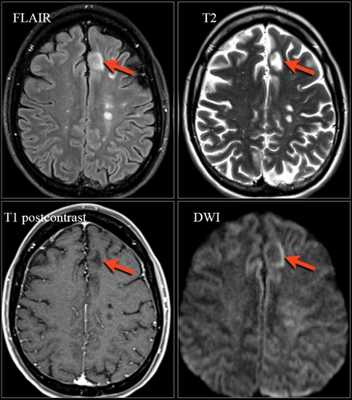

Ключевые диагностические признаки при этой форме ПМЛ:

- Фокальные либо мультифокальные зоны в подкорковом белом веществе, расположенные супратенториально с вовлечением дугообразных волокон и серого вещества коры; менее часто поражается задняя черепная ямка и глубокое серое вещество

- Характеризуются гиперинтенсивным сигналом на Т2

- На Т1 участки могут быть гипо- или изоинтенсивными в зависимости от степени выраженности демиелинизации

- Примерно у 30% пациентов с ПМЛ очаговые изменения усиливаются при контрастировании. Высокая интенсивность сигнала на DWI, особенно по краю очагов, отражает активный инфекционный процесс и отек клеток

На МРТ видны признаки ПМЛ, обусловленной приемом натализумаба. Изображения любезно предоставлены Bénédicte Quivron, Ла-Лувьер, Бельгия.